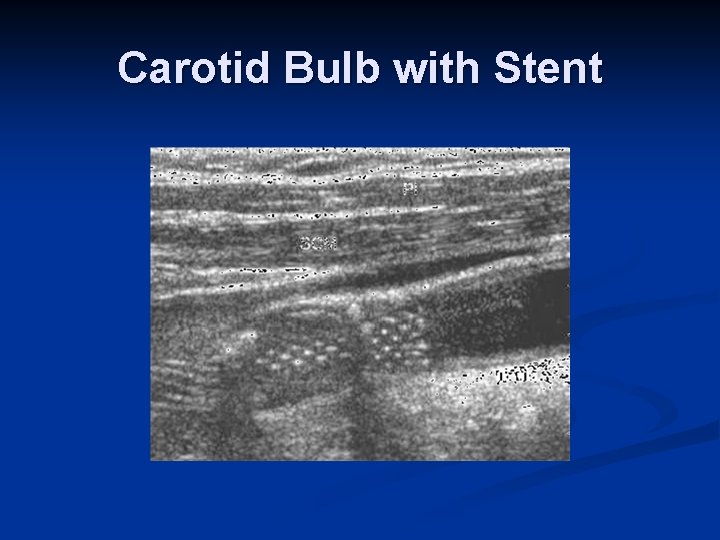

Carotid Bulb with Stent